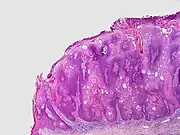

| Subtype (and alternative names) | Characteristics | Image |

| Common seborrheic keratosis (basal cell papilloma, solid seborrheic keratosis) | Dull or lackluster surface.[2]: 769 | |

| Reticulated seborrheic keratosis (adenoid seborrheic keratosis) | Dull or lackluster surface, and with keratin cysts seen histologically.[2]: 769 | |

| Stucco keratosis (deratosis alba,[13] digitate seborrheic keratosis, hyperkeratotic seborrheic keratosis, serrated seborrheic keratosis, verrucous seborrheic keratosis) | Common. Dull or lackluster surface, and with church-spire-like projections of epidermal cells around collagen seen histologically.[2][3] Stucco keratoses are often light brown to off-white, and are no larger than a few millimeters in diameter. They are often found on the distal tibia, ankle, and foot.[12] | |

| Clonal seborrheic keratosis | Dull or lackluster surface, and with round, loosely packed nests of cells seen histologically.[2]: 769 | |

| Irritated seborrheic keratosis (inflamed seborrheic keratosis, basosquamous cell acanthoma) | Dull or lackluster surface.[2]: 769 | |

| Seborrheic keratosis with squamous atypia | Dull or lackluster surface, and with round, loosely packed nests of cells seen histologically.[2]: 770 | |

| Melanoacanthoma (pigmented seborrheic keratosis) | Dull or lackluster surface.[2]: 770 [3]: 687 It involves a proliferation of keratinocytes and melanocytes.[14] | |

| Inverted follicular keratosis[notes 1] | Asymptomatic, firm, white–tan to pink papules[13] Microscopically it is characterized as a well-circumscribed inverted acanthotic squamous proliferation containing squamous eddies and without significant atypia.[15] |  |